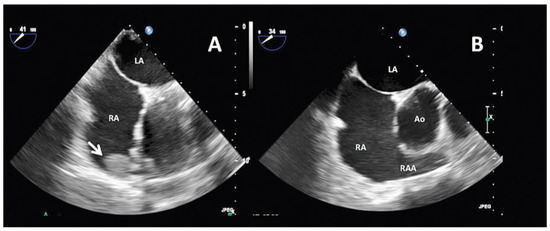

Atrial fibrillation is a cause of left atrial thrombus leading to cardioembolic stroke, which can be effectively prevented with oral anticoagulation. Right atrial appendage thrombus is a rare complication of atrial fibrillation that can also lead to cardioembolic pulmonary embolism. We present the [...] Read more.

Atrial fibrillation is a cause of left atrial thrombus leading to cardioembolic stroke, which can be effectively prevented with oral anticoagulation. Right atrial appendage thrombus is a rare complication of atrial fibrillation that can also lead to cardioembolic pulmonary embolism. We present the case of a 71-year-old male with atrial fibrillation, thrombus in the right atrial appendage and pulmonary embolism. Full article

Show Figures

Figure 1